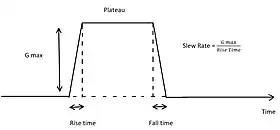

In general, real time MRI relies on gradient echo sequences, efficient k-space sampling, and fast reconstruction methods to speed up the image acquisition process.[10] Gradient echo sequences present shorter echo times since only one RF pulse is required for each sequence.[11] Modern fast-switching gradient coils also require increasing the slew rate, allowing for faster changes in gradient echo sequences and decreasing the repetition time.[12]

Gradient-echo sequences